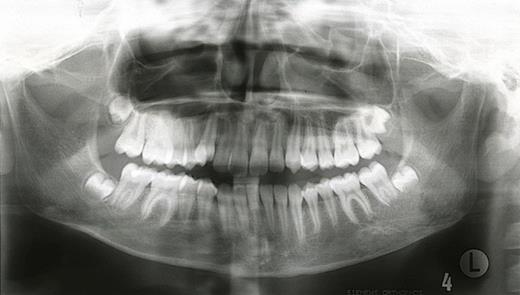

In April 2002 a general dental practitioner referred a 10-year old girl with mandibular asymmetry associated with a 6mm midline shift to the right and a Class 3 skeletal and incisor relationship. Radiographs at initial presentation showed no bony abnormalities and study models were taken, followed by a period of growth monitoring.

In October 2007, the patient represented with a swelling around the left angle of the mandible. Radiographs revealed no abnormalities but oral antibiotics were commenced with the clinical impression being that of osteomyelitis. Over the following month the swelling fluctuated in size, therefore a CT scan was undertaken. This showed a cystic enlargement at the left angle of the mandible with no cortical disruption or soft tissue involvement. With symptoms persisting the patient underwent exploration of the area under general anaesthesia and histopathology (which had previously been negative) now revealed desmoplastic fibroma.

A desmoplastic fibroma often behaves in an aggressive manner and macroscopically has a firm consistency with well-defined advancing surfaces that may extend into surrounding soft tissue. It is usually seen radiographically as a well-demarcated, radiolucent lesion. However, CT and MRI offer the best imaging of the lesion(5). The initial facial asymmetry in this case was most likely caused by the desmoplastic fibroma that was not evident on plain radiographic imaging. Further to this the lesion was not clinically active in the 4 years pre-operatively or evident at osteotomy. It was only in the post-operative period that the lesion was diagnosed, albeit following an initial negative histology